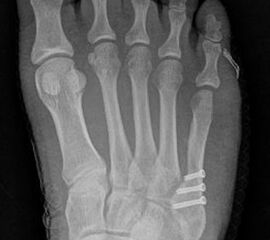

Abb. 7 a, b: Typ II Deformität mit prä- (a) und postoperativem Röntgenbild (b) mit K-Draht Osteosynthese und gleichzeitiger Hallux valgus Korrektur.